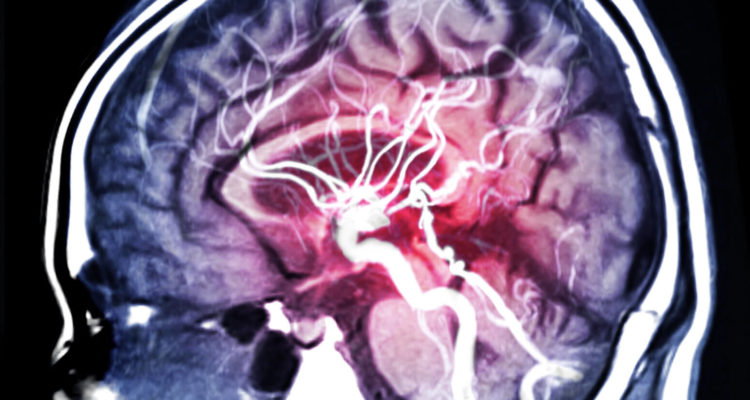

Вчені назвали групи крові, у яких підвищений ризик інсульту у жінок

Група крові, відмінна від I, може збільшити ризик інсульту у жінок, які палять і приймають оральні контрацептиви. Такі дані були отримані в рамках попереднього дослідження.

Оральні контрацептиви можуть підвищувати ризик інсульту у деяких жінок, особливо у курців. Через це пацієнткам старше 35 років, які курять, не рекомендується прийом даних препаратів. Попередні дослідження показали, що групи крові з II по IV також можуть збільшувати ризик інсульту.

Вчені виявили, що у жінок, які курили і приймали оральні контрацептиви, ймовірність інсульту була майже в п’ять разів вище, ніж у жінок, які не приймали препарати і не мали шкідливої звички. Група крові, крім I, ще більше збільшила ризик раннього інсульту у жінок, які курили та приймали оральні контрацептиви. Йшлося про підвищення ризику майже в два рази.